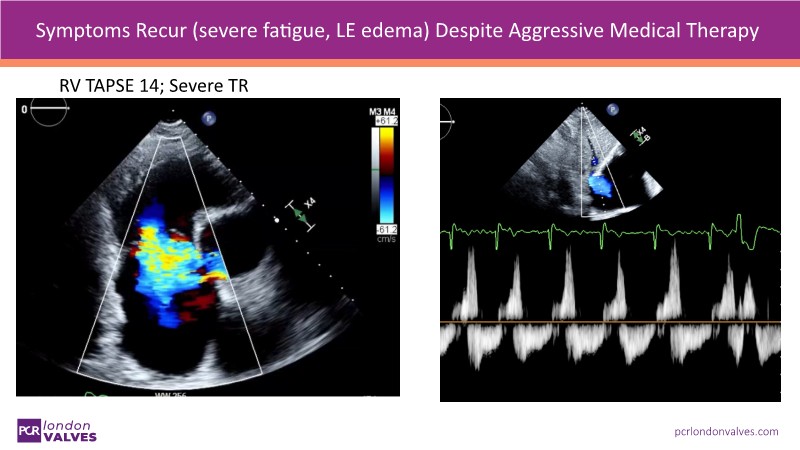

This session decodes the advancement of caval valve therapy with the TricValve system, offering novel solutions for tricuspid regurgitation and right heart failure. It incorporates insights from clinical trials, real-world cases, and guideline integration, detailing imaging techniques and strategies for complex patient management including rescue interventions.

- To discover how TricValve is providing answers in tricuspid regurgitation and right heart failure where no other therapies could

- To gain first-hand insights from real-world cases, clinical studies, and pioneering United States and European experiences with caval valve therapy